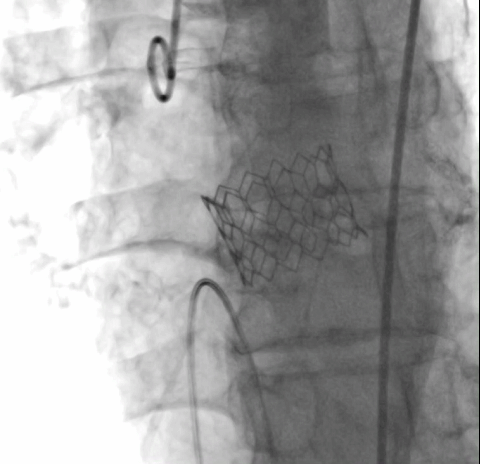

瓣膜“0位”释放 术后主动脉根部造影

经术前详尽影像学重建、评估及病例讨论,最终决定在脑氧监测下对患者实施经左侧颈总动脉TAVI手术。术中左侧颈总动脉多次预扩后顺利置入血管鞘至升主动脉,跨瓣成功后先以23#球囊预扩,再“0位”植入25# Renatus介入主动脉瓣。手术耗时约2小时,介入主动脉瓣植入位置理想,功能表现良好,主动脉瓣峰值流速及平均跨瓣压差分别降至1.75m/s和5mmHg,造影及TEE观察仅有轻微瓣周漏,无中央型反流。术后左颈总动脉造影无明显狭窄,手术全程脑氧饱和度正常,无传导阻滞、无冠脉异常。